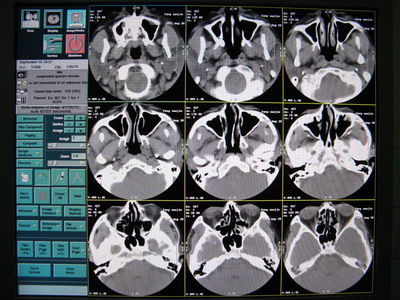

6.原因會不會是數(shù)據(jù)到了 OC 這邊重建出了問題呢,用原來正常圖像的原始數(shù)據(jù)用相同的條件進行重建,發(fā)現(xiàn)正常圖像的原始數(shù)據(jù)重建出來的圖像出現(xiàn)了偽影,如下圖:

正常的圖像

重建出來的偽影圖像

7.用原來掃出來不正??諝鈭D像的原始數(shù)據(jù)用相同條件反復重建如下圖:

從上面幾幅圖可以看出,每次重建出來圖像出現(xiàn)偽影的地方都不同,原來不正常的圖像可以重建出正常的圖像,再次證明了原始數(shù)據(jù)是沒有問題的。